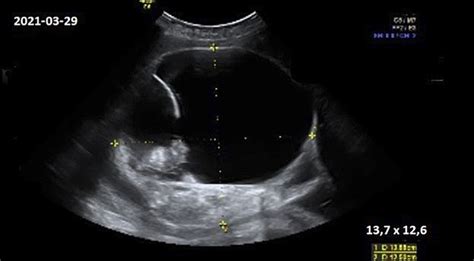

Pirmąjį trimestrą ultragarsas yra pasirinkimo metodas: jis patvirtina embriono gyvybingumą, atmeta negimdinį nėštumą ir leidžia vizualizuoti subchorioninę hematomą. Antroje nėštumo pusėje retroplacentinės hematomos atveju ultragarso jautrumas yra ribotas, todėl hematomos nematymas neatmeta vaisiaus atsitraukimo. Diagnozė ir gydymas grindžiami simptomais, motinos ir vaisiaus būkle, kraujo netekimo kiekiu ir jo dinamika.

Terminas „hematoma nėštumo metu“ apima keletą skirtingų kraujo sankaupų tarp kiaušialąstės membranų, placentos ir gimdos sienelės, kurios skiriasi savo vieta ir reikšme. Pirmąjį trimestrą dažniausiai nustatoma subchorioninė hematoma, susijusi su daliniu choriono atsiskyrimu. Antrąjį ir trečiąjį trimestrus nustatomos subamnioninės, subchorioninės, intra- ir retroplacentinės hematomos, o retroplacentinė hematoma dažnai atitinka klinikinį placentos atitrūkimo vaizdą normaliai išsidėsčiusioje placentoje. Šios būklės skiriasi prognoze ir stebėjimo taktika.

Subchorioninė hematoma (SCH) yra būklė, kai nėštumo metu kraujas kaupiasi tarp gimdos sienelės ir placentos. Subchorioninė hematoma - tai kraujo susikaupimas tarp gimdos sienelės ir chorioninės membranos nėštumo metu. Chorioninė membrana yra išorinis sluoksnis, atskiriantis vaisiaus amniono maišelį nuo gimdos sienos. Subchorioninė hematoma atsiranda, kai kraujas kaupiasi tarp choriono (išorinės membranos, supančios embrioną) ir gimdos sienelės. Ši būklė būdinga ankstyvuoju nėštumo laikotarpiu ir gali būti įvairaus dydžio.

Subchorioninė hematoma yra dažniausias ultragarsinis radinys gyvam embrionui per pirmąjį trimestrą. Ji išsivysto dėl chorioninio prisitvirtinimo mikrotraumos ir paprastai išnyksta savaime. Dauguma nėštumų, kuriems pasireiškia subchorioninė hematoma, baigiasi sveiko vaisiaus gimimu, ypač jei hematoma yra maža.